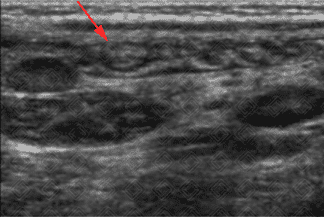

Texto alternativo para a imagem Figura 2. Créditos: Dra. Elazir Mota - Rio de Janeiro/RJ

Descrição das figuras 1 e 2: Ultrassonografia de abdome com múltiplos e grandes linfonodos mesentéricos, hipoecogênicos, com espessamento de alças associado (seta vermelha). Ao estudo com Doppler colorido podemos observar aumento da vascularização do mesentério, sugerindo processo inflamatório/infeccioso. [cms-watermark]

• Na ultrassonografia de abdome: Observam-se múltiplos e grandes linfonodos mesentéricos, hipoecoicos, com aumento da ecogenicidade da gordura mesentérica. Vale destacar que esses linfonodos possuem morfologia e vascularização preservadas ao Doppler colorido. Na população pediátrica, o exame de escolha será a ultrassonografia de abdome.